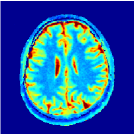

Two sets of experiments were conducted here: first, we used the 2D and 3D acquisition sequences for scanning a healthy volunteer’s brain (real-world acquisitions). Figures 6 and 7 display the parametric maps reconstructed from 2D spiral and radial readouts. We computed the T1, T2 and proton density (PD) maps using baseline reconstruction algorithms ZF, VS, LR, FLOR, AIR-MRF and our proposed LRTV. While baselines use DM either for quantitative inference or also during reconstruction (i.e. AIR-MRF), we further compare the DM-free LRTV’s performance when cascaded to DM, KM and MRFResnet for quantitative inference. For the 3D spiral acquisitions we compared LRTV and its closest competitor VS in Figure 8. Outcomes from other tested algorithm are displayed in the supplementary materials (Figure S5). Since FLOR does not use dimensionality-reduction, our system ran out of memory during 3D reconstruction; hence results are not reported in this case.

The LRTV-DM and LRTV-MRFResnet perform on par, and both outperform all tested baselines for reconstructing T1, T2 and PD maps in all acquisition schemes. This can be observed both visually in Figures 6, 7, 8, S2 and S3, and quantitatively in Table IV across all tested metrics. Other baselines were unable to successfully remove the under-sampling artefacts in TSMIs, and these errors propagated to the parameter inference phase and resulted in inaccurate maps. Temporal-only priors incorporated within LR are shown insufficient to regularise the inverse problem and LR sometimes (e.g. 2D spiral acquisitions) can admit solutions with even stronger artefacts than the model-free ZF baseline. This issue was previously studied for other non-Cartesian MRF readouts that similar to our spiral/radial trajectories, miss to sample the corners of the k-space in all timeframes (see section 2.2.2 and figure 2 in [19]). In the absence of reference for the k-space corners information, the LR iterations despite minimising the objective can converge to solutions with high-frequency artefacts, as visible in the computed maps. This highlights the need for adding an appropriate spatial-domain regularisation. FLOR reduces the LR’s artefacts but this improvement is limited because the suggested nuclear norm penalty does not incorporate an explicit spatial regularisation. Further for reducing artefacts, FLOR can introduce an undesirable bias in the computed T1/T2 maps e.g. see error maps in Figures S2 and S3. The non model-based VS baseline incorporates spatial regularisation and results in spatially smoother maps than ZF and LR, but it is unable to output artefact-free images. Further and consistent with our in-vitro experiment, we observe that VS overestimates the T2 values (e.g. in White and Grey matter regions) in tested 2D acquisitions i.e. the spatial regularisation trades off agains the quantification accuracy. The model-based AIR-MRF adds spatial regularisation through 2D/3D low-pass Gaussian filters however this trades off the sharpness of the computed maps and can increase the errors at the tissue boundaries (we searched Gaussian spreads that keep the blurs and high-frequency artefacts minimal). For our acquisition readouts, Gaussian filters performed better than disk filters of [19] for avoiding strong Gibbs artefacts. On the other hand, the spatiotemporally regularised LRTV greatly improves the TSMI reconstructions i.e. 4 dB enhancement compared to the closest competitor baseline (Table IV). This enables computing accurate and aliased-free multi-parametric inference using DM or the DM-free learning-based alternative MRFResnet as visible in Figures 6, 7, 8, S2 and S3. MRResnet and DM score competitive quantitative inference results i.e. T1 and T2 MAPE less than 5% and 9%, respectively (Table IV). KM also outputs comparably accurate T1 maps, however this shallow learning model despite having a model size larger than MRFResnet, is unable to learn accurate T2/PD quantification and it results in poor estimated maps, consistent with our observations in section VI-C.